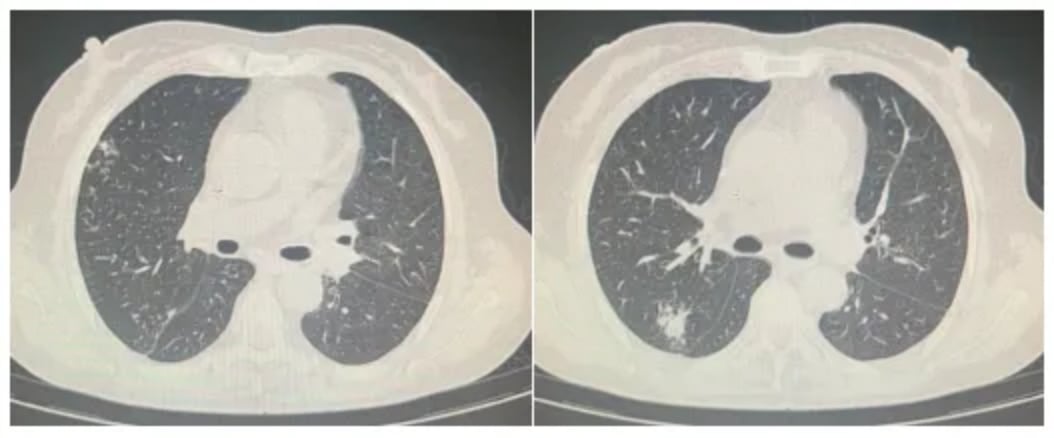

该患者确诊为PCNS-DLBCL后,接受了长达10个疗程的大剂量甲氨蝶呤联合替莫唑胺治疗。然而,在化疗结束后6个月首次复发,接受放疗后10个月再次复发,病情十分棘手。

这位66岁的女性患者在接受标准的R+HD-MTX方案治疗后,因故停药3个月后出现疾病进展。后续调整方案后,病情再次恶化,出现头痛、恶心、呕吐等严重症状。